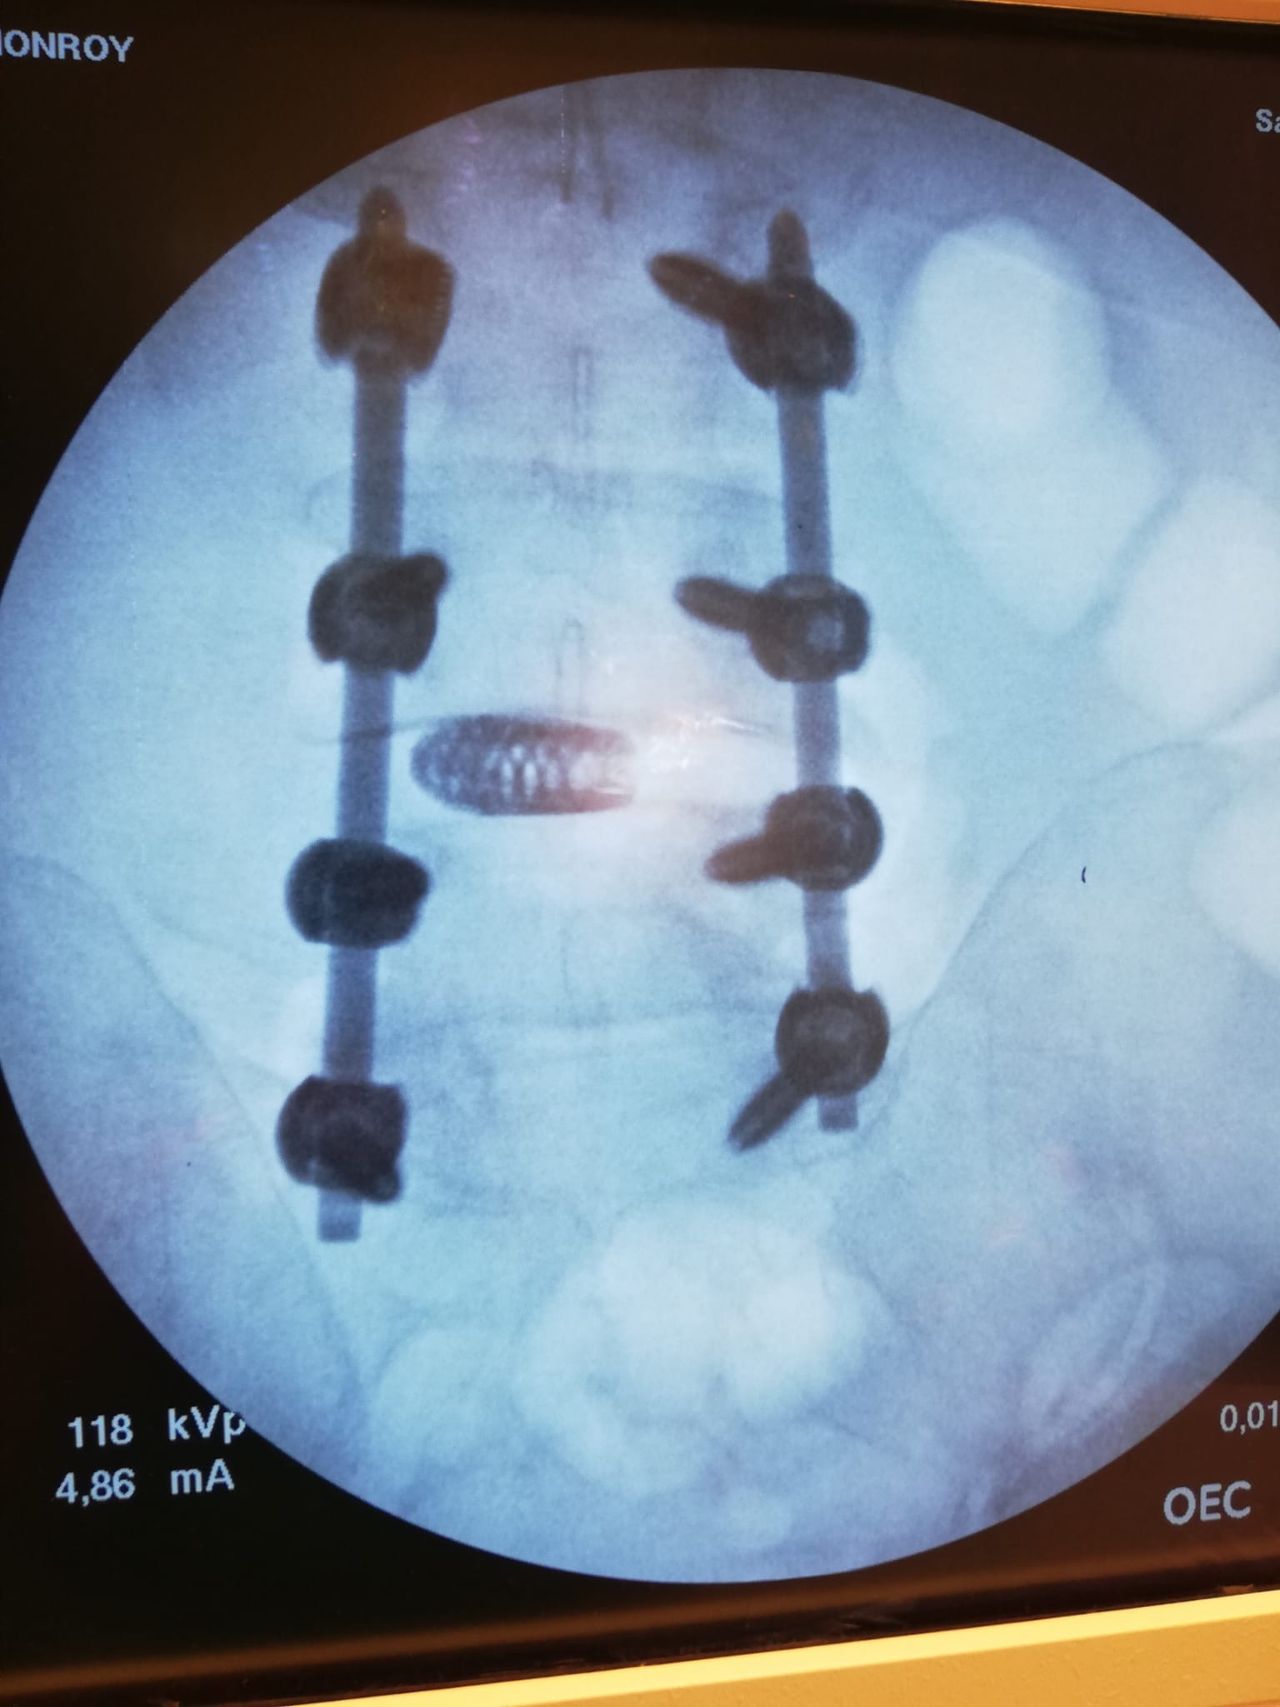

- Chirurgia Mininvasiva percutanea vertebrale - stabilizzazioni e artrodesi intersomatiche (per fratture vertebrali, spondilolistesi, instabilità vertebrali, discopatie)

- Impianti protesici di ultima generazione, massima integrazione con l’osso e maggiore durata negli anni

- RX scopia intraoperatoria